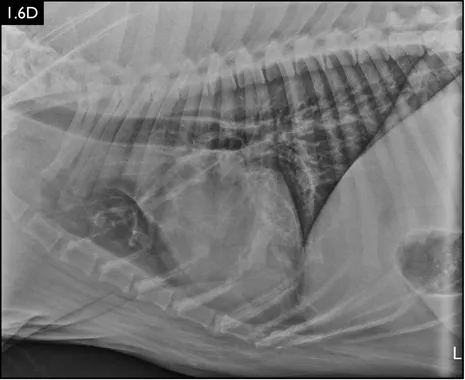

Clinical signs can be strongly suggestive of bacterial pneumonia, but radiographs are important for confirmation, to characterize the disease (and potential etiology) and to provide a baseline for monitoring response to treatment (Figs. 1.4–1.6). A lag between clinical signs and radiographic changes can occur, and initial radiographs may be normal or appear discordant with clinical severity.

Fig. 1.4A–D Lateral and ventrodorsal radiographs of a dog with doxycycline-responsive pneumonia of unknown etiology before treatment ( A, B) and six days later ( C, D). Note the severe multilobar alveolar pattern that was present initially, most prominently in the left cranial lung lobe. (Courtesy of Atlantic Veterinary College)

Fig. 1.6A–D Radiographs of a dog with suspected aspiration pneumonia. A diffuse alveolar pulm...